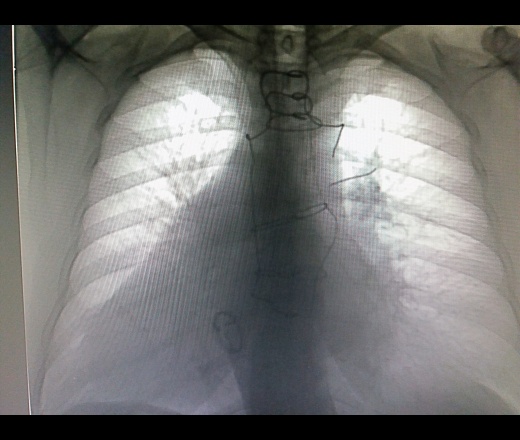

Мужчина 1950 г р. Проф ФЛГ. Операция по поводу имплантации искуственного клапана. Читал снимки и вот такое обнаружил! Слетела проволока с грудины:(. Коллеги посмотрите пожалуйста может кто видел подобное? Что делать?

Кардиохирургия, имплантированный митральный клапан.Дефект металлоконструкции.

Можно написать "разрыв серкляжного шва". Назначить рентгенографию грудины в 2 проекциях, что бы посмотреть куда мигрировала эта фигнюха. Иногда они впиваются в мягкие ткани и вызывают отек и боли...